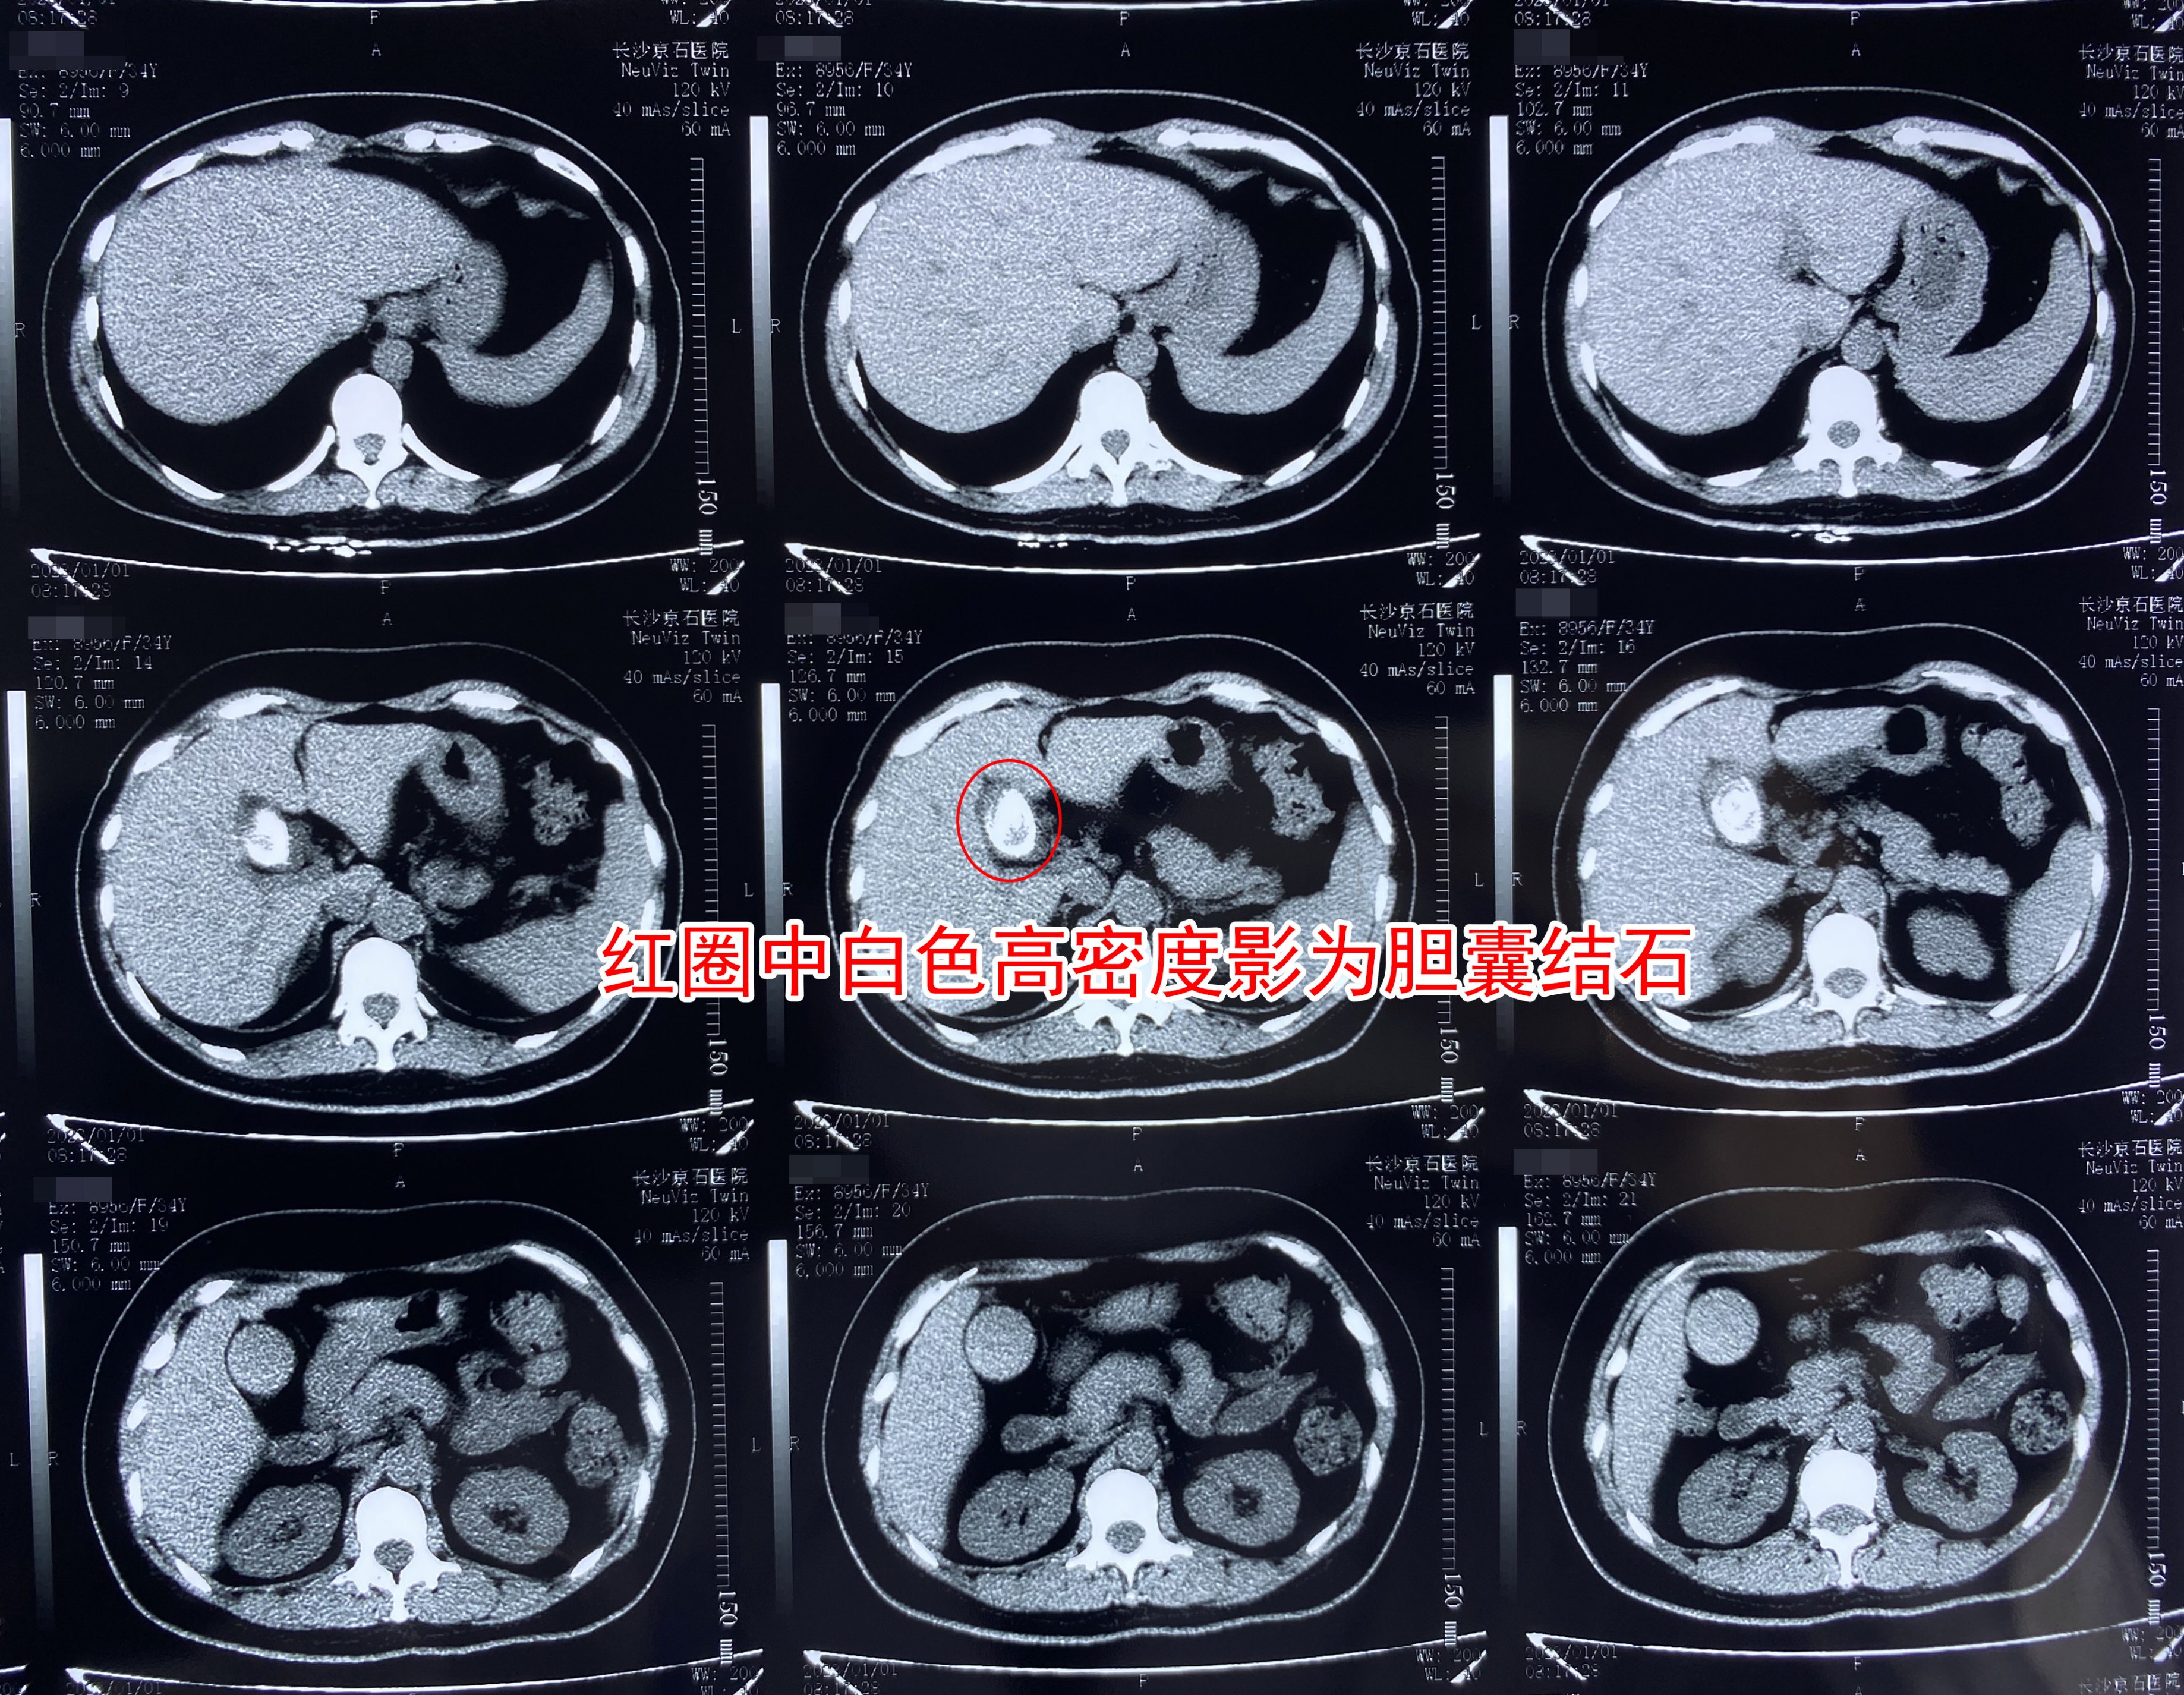

(王女士术前CT检查结果局部图)

12月31日,王女士来到长沙京石医院就诊。入院后接受了初步检查,确诊患有胆囊结石并胆囊炎,不仅结石最长径达3.2公分,且胆囊中有大量的胆汁淤积,已达到了手术治疗指征,于是王女士立即办理了入院手续。